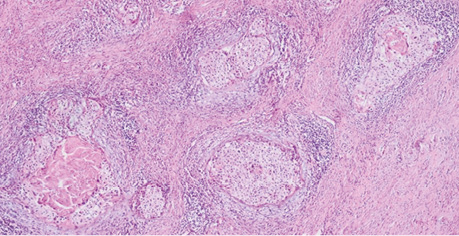

Взято біопсію шийки матки. Патогістологічний висновок: у матеріалі біопсії з урахуванням результатів морфологічного та ІГХ дослідження серед крові визначаються фрагменти тканини шийки матки, інфільтровані елементами інвазивної плоскоклітинної HPV-асоційованої карциноми G1 (low grade) (рис. 1).

Рис. 1. Рак шийки матки — інвазивна плоскоклітинна HPV-асоційована карцинома G1 (low grade)

Фрагмент тканини шийки матки переважно заміщений розростаннями злоякісних епітеліальних клітин, диспластичний багатошаровий плоский епітелій через базальну мембрану поширюється в прилеглу волокнисту сполучну тканину без прикріплення до поверхні, клітини пухлини з вогнищевим плеоморфізмом, наявні фігури мітозів, некрози відсутні, клітини пухлини з крупними гіперхромними базофільними ядрами та переважно скудною еозинофільною цитоплазмою, з наявністю внутрішньоклітинних містків, пухлина солідно-гніздового типу росту, без ознак ороговіння, без формування кератинових мас (рис. 2).